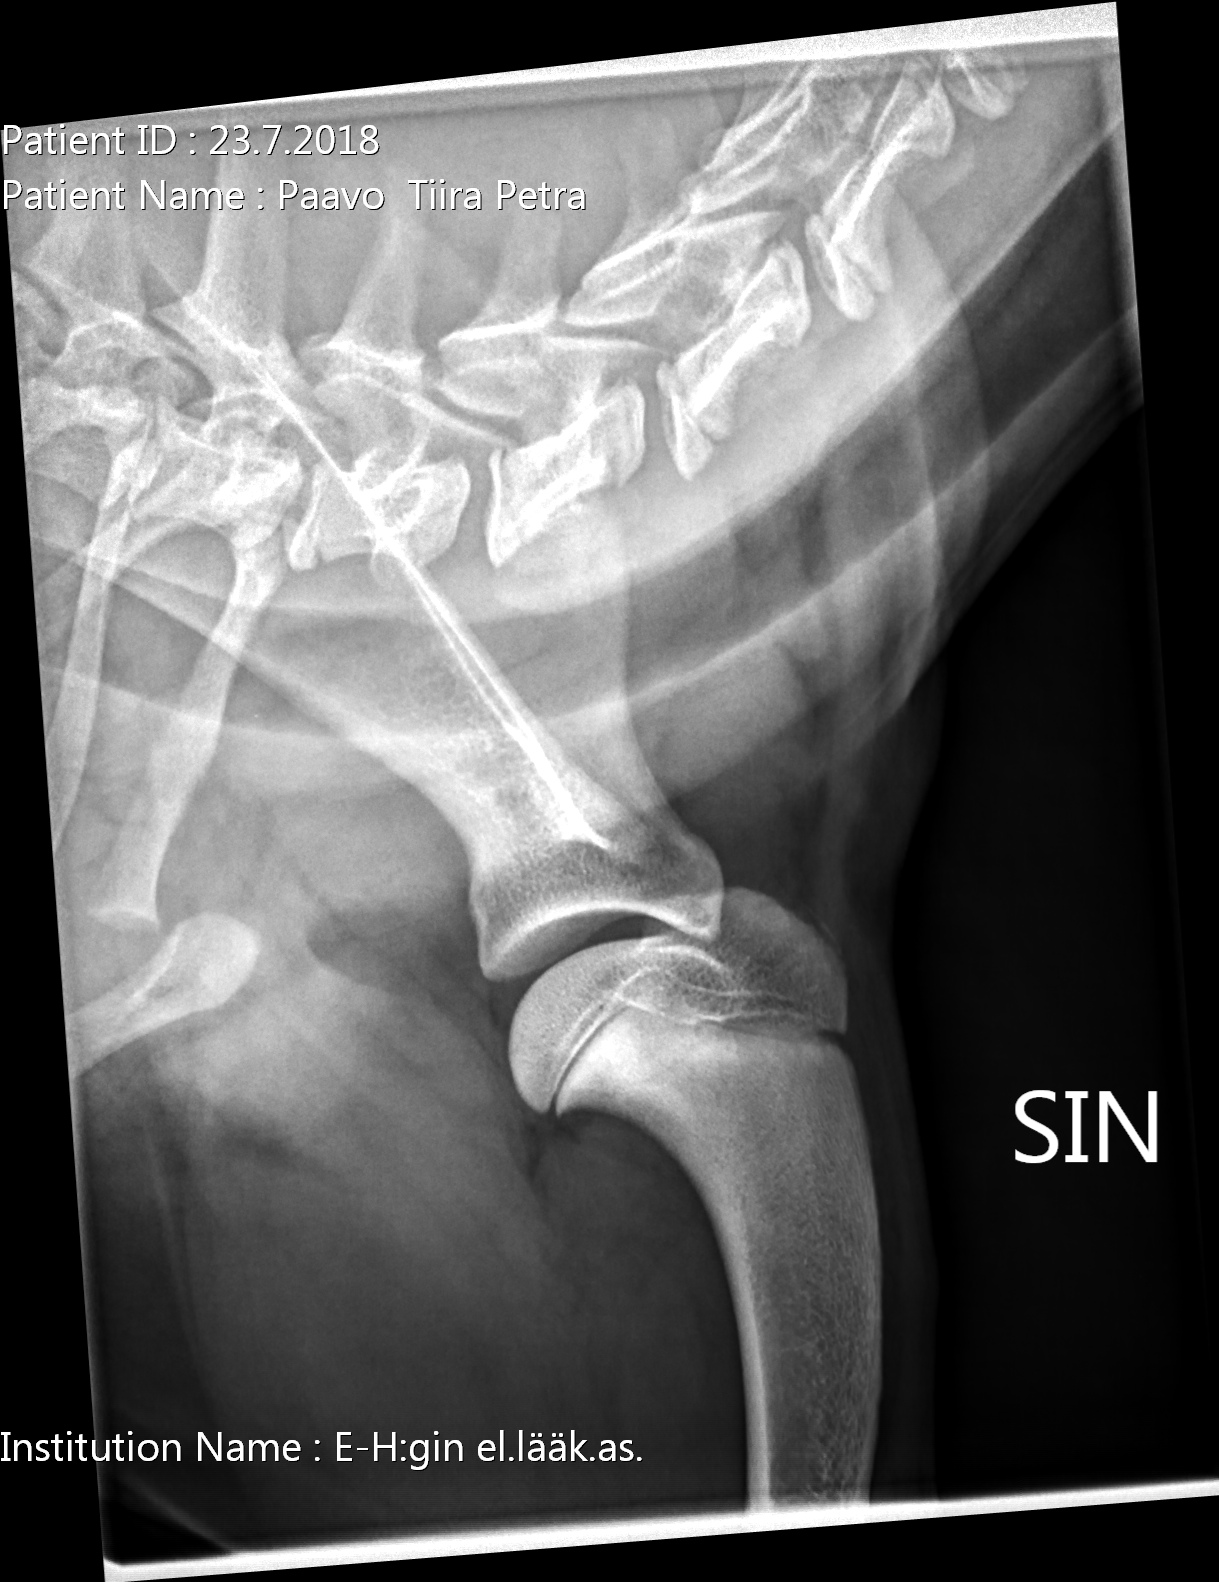

Paavon terveet olat ja kyynärät, aavistuksen erilaatuiset kuvat kuin aiemmat, ja kuten huomaatte, asettelu olkakuviin erilainen. Edelleen kovin sileät ja pyöreät nivelpinnat.

Paavon ensimmäiset kuvat: Ja näitä sitten tihrustin vaikka mitenpäin, niin en ymmärtänyt missä se vika on, kun nivelpinnat ovat ihan sileät ja pyöreät? Toki en nyt ortopedi olekaan. Ps. jos teitä ihmetyttää alemman kuvan kyynärän "irtonainen" kärki, kuuluu asiaan. Ei ole vielä luutunut 20-viikkoisella nuo kohdat. Itsellä ainakin sydän meinasi pysähtyä, kun en aiemmin näin nuoren koiran röntgenkuvia ole katsellut.